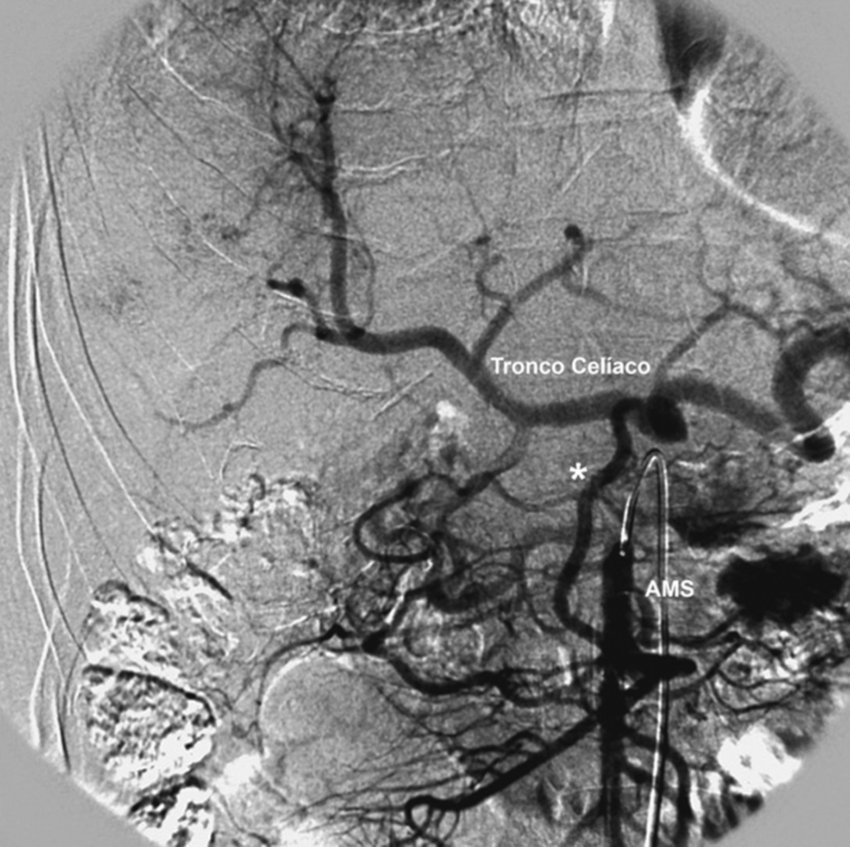

Tipo 9: la AHC emerge de la AMS (Fig. 17).

Además, se observaron variantes fuera de la clasificación de Michels en 6 casos (2.2%): ausencia del tronco celíaco en 3 casos, tronco celíaco mesentérico en 2 casos (Fig. 18), y arterias hepáticas aberrantes derecha e izquierda originarias de AMS en 1 caso. Asimismo, en 3 casos de la variante tipo 1 de Michels se observaron los hallazgos asociados del arco de Bühler (Fig. 19).